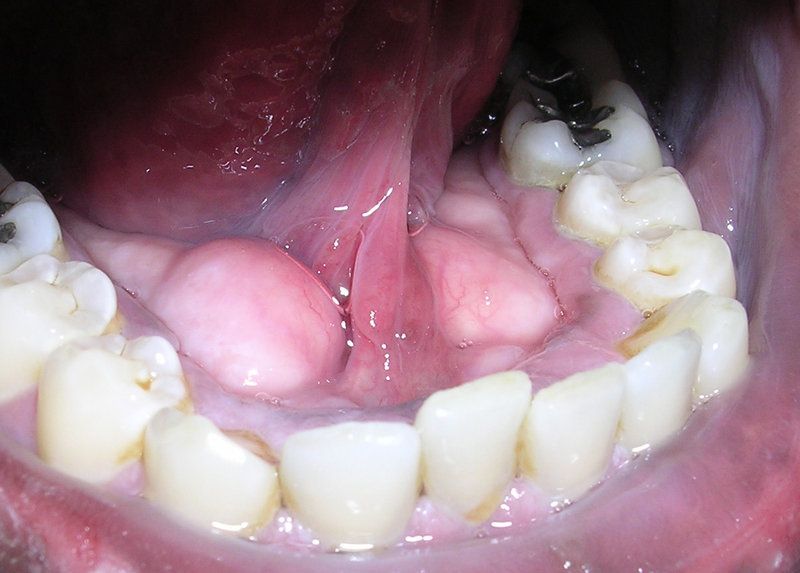

This plaque is made up of glycogen (a carbohydrate). With the formation of this plaque, the bacteria can easily adhere, and consequently produce large amount of acids that demineralizes the enamel i.e it removes the calcium that makes the enamel very strong. Once it achieves this, then caries (tooth decay ) begins and the bacteria can then penetrate deeper into the tissues and gum supporting the teeth, this causing serious pain and inflammation

I will like you to note that most tooth decay occurs mostly at those teeth located at the back or inner part of the mouth where this bacteria are enormous in number. It occurs mostly in the premolars and the molars. View pics for better understanding. The black substance on the teeth is the plaque.